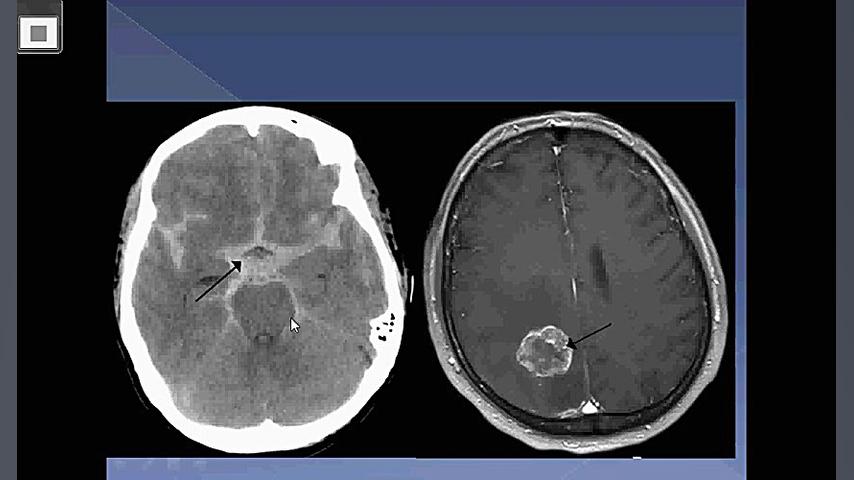

جراح مغز و اعصاب وستون فقرات جراحی های کم تهاجمی ستون

اعصاب

مغز

سلامت مغز و اعصاب